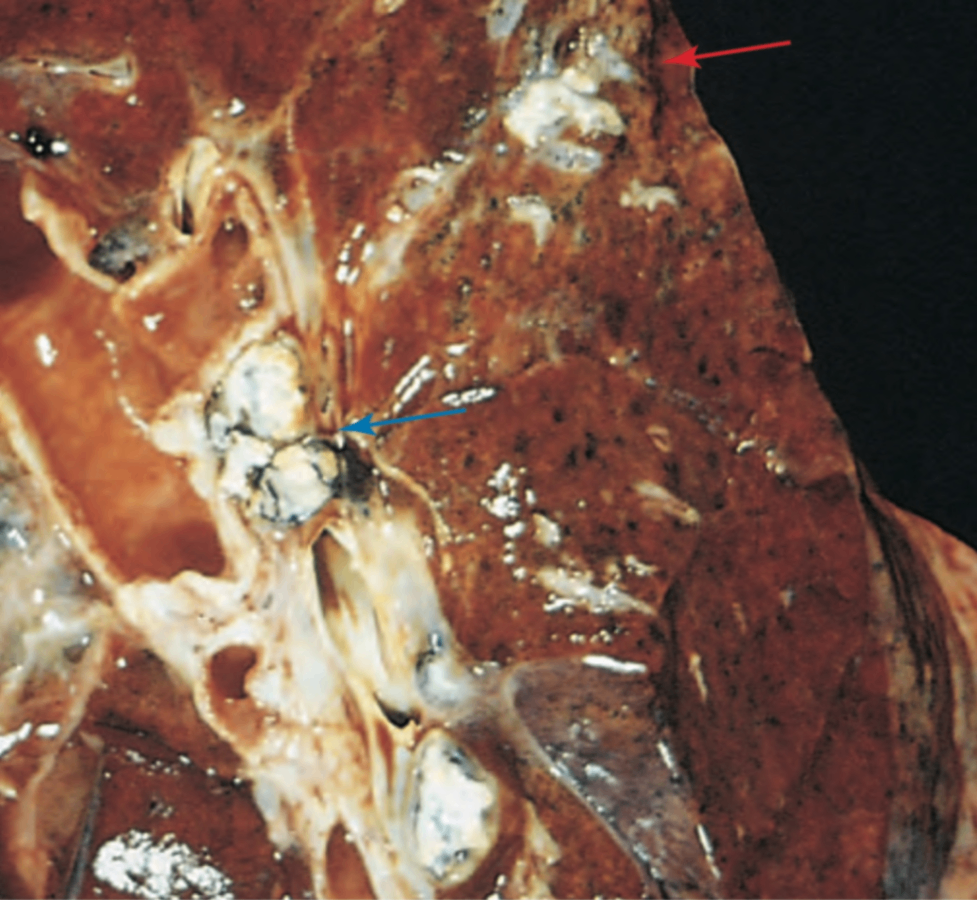

③ 진행석 폐결핵 (progressive pulmonary tuberculosis)

면역저하자나 고령에서 흔하며 상엽 첨부의 병변이 기관지와 혈관을 침범해 발생

• 이로 인해 공동이 형성되는데, 폐 조직의 심각한 파괴를 유도하며 섬유화를 통한 경계가 명확하지 않음

• 혈관 침범으로 인해 객혈 발생 가능